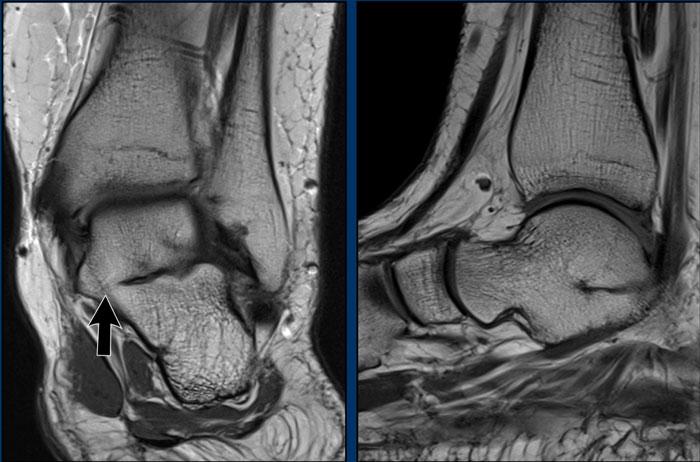

Hình ảnh

Trên hình ảnh T1W, có sự hợp nhất xương và cứng khớp của xương sên với xương gót.